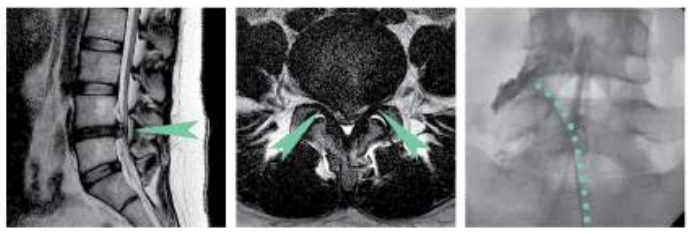

사무직에 종사 중인 환자는 평소에도 가벼운 요통이 있었지만 걷거나 움직이면 통증이 호전되었기 때문에 대수롭지 않게 여겼다고 하셨습니다. 하지만 스윙 동작 중 순간적으로 척추 아랫쪽 심한 통증으로 병원을 찾으셨습니다. 허리 통증 뿐 아니라 엉덩이를 타고 다리까지 이어지는 저림 증상으로 운동 마비를 동반해 걷기 힘든 상태였습니다. 일상 생활이 불가할 정도의 급성 허리 통증과 신경학적 증상이 있기에 환자 X-ray 촬영과 MRI 검사를 진행했으며 요추 4-5번 디스크 탈출을 진단 내렸는데요, 탈출한 디스크가 터져 신경을 심하게 누르고 있는 것을 확인할 수 있었습니다.

먼저 CI 주사치료를 진행했습니다. 허리신경차단술 CI치료는 특수영상촬영장비인 C-arm을 통해 병변 부위를 실시간으로 확인하며 진행되는데요, 약물을 주사하면서 신경 주변으로 퍼지는 것을 확인할 수 있어 정확도가 매우 높습니다. 탈출되고 파열된 디스크로 생긴 염증과 붓기를 가라앉히는 효과를 기대할 수 있습니다. 해당 환자의 경우 디스크 탈출증과 협착증이 같이 보이는 소견으로 CI 치료에는 미미한 반응을 보여 신경성형술인 PEN 시술 후 만족스러운 호전이 있으셨습니다. PEN 시술은 지름 2mm의 매우 가느다란 특수 카테터를 삽입해 약물을 직접 주입하는 방법으로 수술적 치료법 이전에 마지막으로 시도해볼 수 있는 비수술 치료방법입니다.